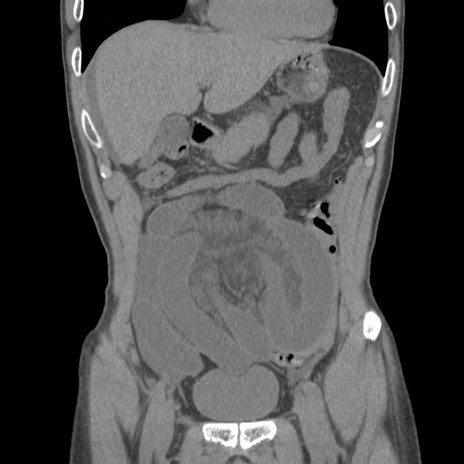

症例56 CT(冠状断像)

横断像